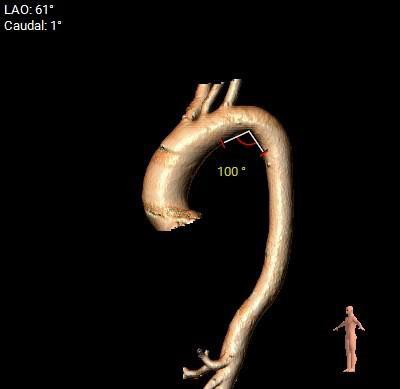

主动脉弓测量:

主动脉弓部宽度、角度可。

主动脉瓣水平夹角约57°,非横位心,主动脉弓宽度角度可;